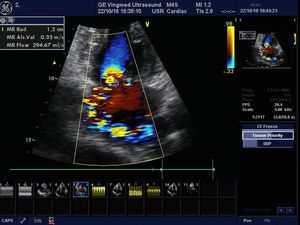

Mitral regurgitation

SMC heart clinic in Cambodia